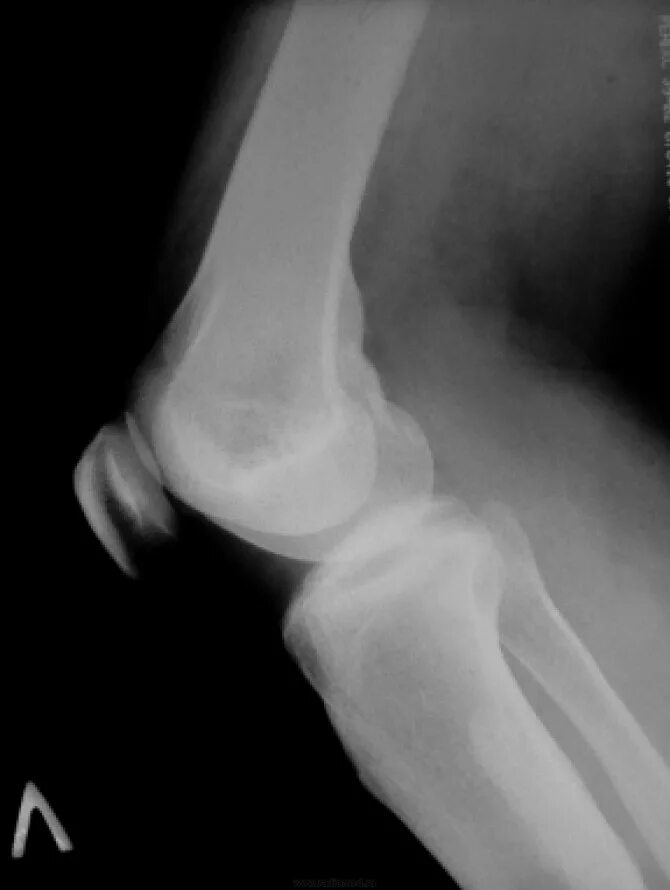

Остеосклероз суставов